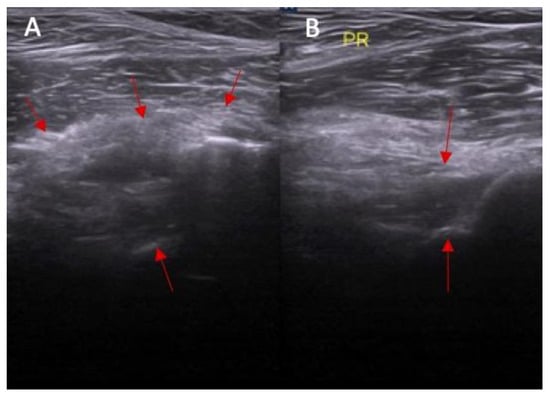

Figure 3.

The inclination of the ACL—the ultrasound view (ACL is marked with red arrows). (A) normal = 45 degrees angle between extension of posterior border of the ACL and base line and (B) abnormal < 40 degrees angle between extension of posterior border of the ACL and base line.

Abnormal inclination of the ACL in ultrasound was noted in 8% of patients without an ACL injury and in 67% of patients with an ACL injury (Figure 3 and Figure 4). Abnormal inclination of the ACL in ultrasound is more common in patients with an ACL injury (p < 0.0001). The odds ratio (OR) was 24 (95% CI and 4.50—127.96).